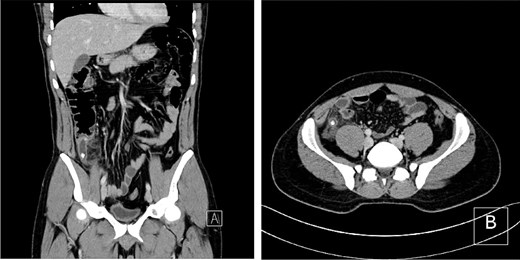

A contrast-enhanced computed tomography (CT) scan of the abdomen revealed an enlarged appendix measuring 1.5 cm in diameter, with an enhancing wall, significant surrounding fat stranding, and intraluminal calcifications, consistent with acute appendicitis (Fig. 1). The patient underwent emergent laparoscopic appendectomy. Intraoperatively, the appendix was inflamed with a sealed perforation and localized contamination; a peritoneal drain was placed surrounding localized contamination; a peritoneal drain was placed.

CT scan showing an inflamed, dilated appendix with surrounding fat stranding and intraluminal calcifications in (A) coronal and (B) axial views.